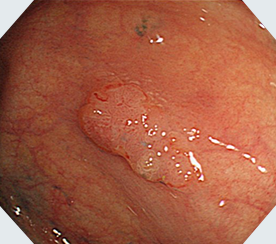

NBI

通常光

NBI+拡大観察

クリスタルバイオレット+拡大観察ハイビジョン対応の高画質で、拡大観察できる光学ズーム機能を搭載。NBIとの併用により、腫瘍などの詳細な観察・診断が可能です。